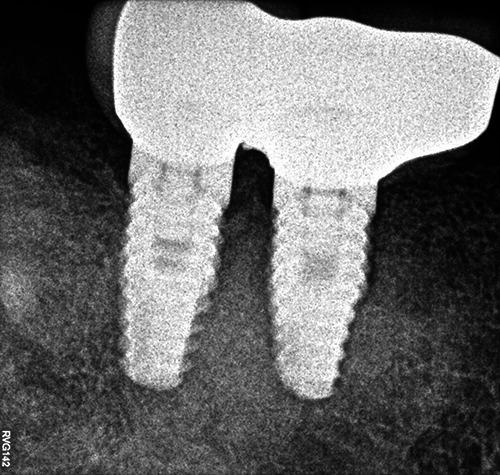

Florid cemento-osseous dysplasia (FCOD) is a rare benign fibro-osseous lesion which affects multiple quadrants and predominantly the mandible. This case report presents a successful implant placement with 8-year of follow-up in a 44-yearold woman asking for a fixed restoration in mandibular right posterior edentulous area. Radiographic images showed lobular, irregularly shaped radiopacities and radiolucencies almost symmetrically observed in the premolar-molar area of the right and left regions of the mandible. The findings of Xray images were attributable to FCOD. Minimally invasive two-stage surgery with strict infection control was followed to place two implants in lower right posterior region. The implants demonstrated clinically rigid fixation and restored successfully after 6 months. A direct functional connection between dysplastic bone and the implant load bearing surface was evidenced by the lack of symptoms, and the lack of soft tissues inflammation or peri-implant bone loss up to 8 years follow-up.

florid骨水泥骨发育异常(FCOD)是一种罕见的良性纤维骨病变,累及多个象限,主要累及下颌骨。本病例报告介绍了一名44岁女性在下颌右后牙无牙区进行固定修复,成功植入种植体并随访8年的情况。影像学图像显示在下颌左右区域的前磨牙-磨牙区几乎对称地观察到小叶状、形状不规则的不透射线区和透射区。X线图像的表现符合FCOD。采用严格控制感染的微创两阶段手术,在下颌右后区域植入两颗种植体。种植体在临床上表现出坚固的固定,并在6个月后成功修复。在长达8年的随访中,没有症状,没有软组织炎症或种植体周围骨丢失,证明发育异常的骨与种植体承载表面之间存在直接的功能连接。